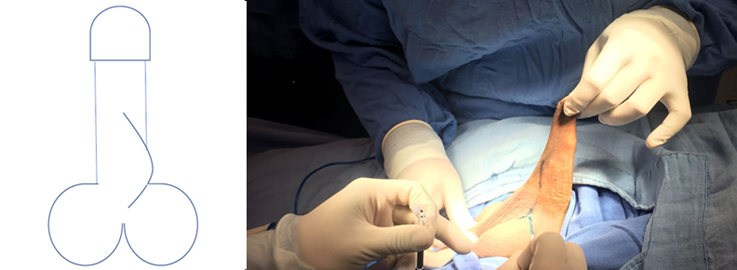

Se realiza protocolo prequirúrgico con documentación completa en el expediente clínico, ingreso del paciente para cirugía ambulatoria, con valoración anestésica, ayuno de 8 horas, baño previo al procedimiento, no se administró antibiótico profiláctico por no estar justificado, se realiza tricotomía según se necesite, se aplica asepsia antisepsia con iodopovidona. Se coloca lidocaína al 2% como anestésico local en el área quirúrgica en planos superficiales y profundos. La técnica quirúrgica aplicada en ambos casos se trata de una Plastia V-T, la cual consiste en realizar una incisión sobre la cuerda en forma de v invertida para despegar las capas de la piel de su adherencia aberrante en la cara ventral del pene (Figura 1 y 2), se afronta la nueva base del pene con sutura absorbible (Figura 3 y 4) , posteriormente se realiza incisiones laterales a la base del pene y coincidiendo a la raíz de la piel del escroto para distribuir toda la piel escrotal sobrante de manera uniforme, esto confiere la forma final de una T invertida (Figura 5 y 6).

Podemos observar que posterior a la realización de la circuncisión, se realizó paso a paso la técnica propuesta como podemos observar en las Figuras 1-6 que corresponden al caso 1 que fue el más representativo de la técnica.